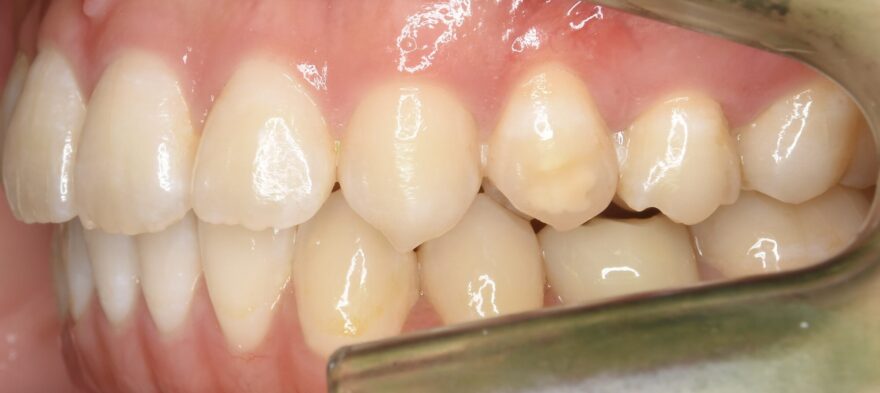

初診時の口腔内写真

上下の歯列の真ん中(正中)が合っていません。

この方向から見ると、前歯が出ていることが分かります。

乳歯の根本が腫れています。

前歯のガタガタが気になります。